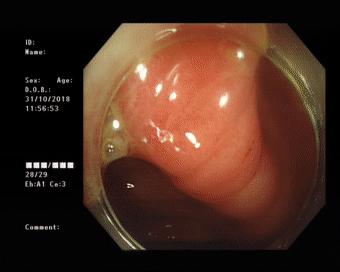

患者做好肠道准备后于30日上午在内镜室进行了内镜下逆行阑尾炎治疗术。术后,患者自诉腹痛明显缓解。

(镜下可见多股絮状脓液流出)